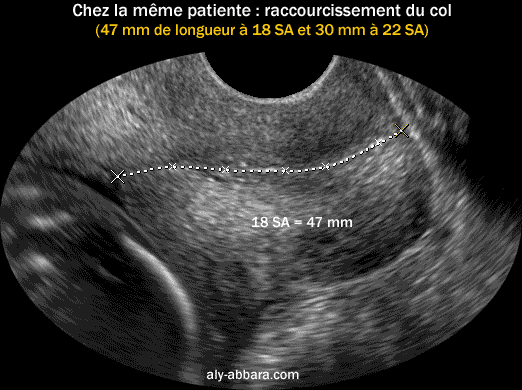

Image échographique montrant l'utilité de l'échographie dans la surveillance du col utérin : le col passe de 47 mm de longueur à 18 SA, à 30 mm à 22 SA en restant cliniquement toujours fermé.

La surveillance du col était nécessaire devant les antécédents obstétricaux de la patiente : modifications précoces du col utérin lors des deux grossesses précédentes avec un accouchement prématuré à 31 SA et à 35 SA (après cerclage du col)